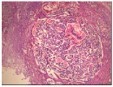

Figure 4.MEN1 syndrome demonstrating a parathyroid adenoma with encapsulation and glandular proliferation13.